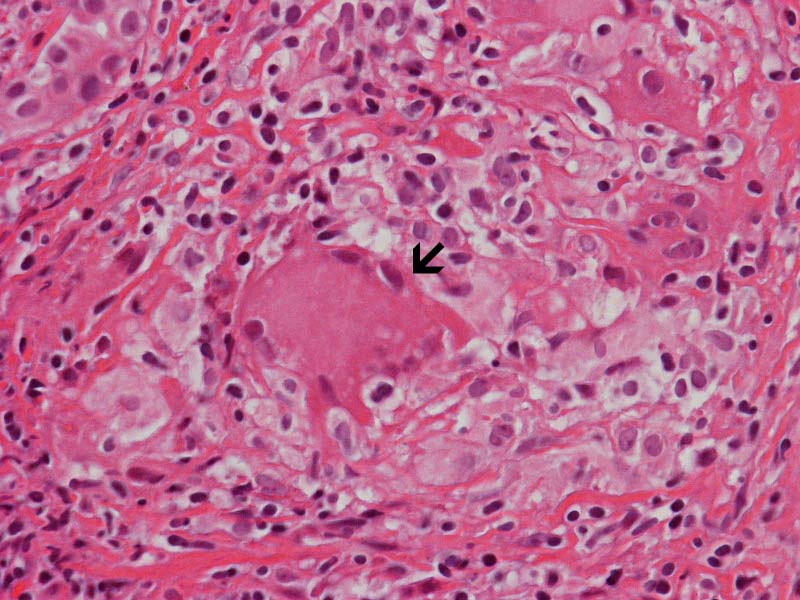

Granuloma: This is another image that show the granuloma (arrow in the left panel). This image provides a good survey on the extent of granulomatous changes. A multinucleated giant cell is present (arrow in the right panel)